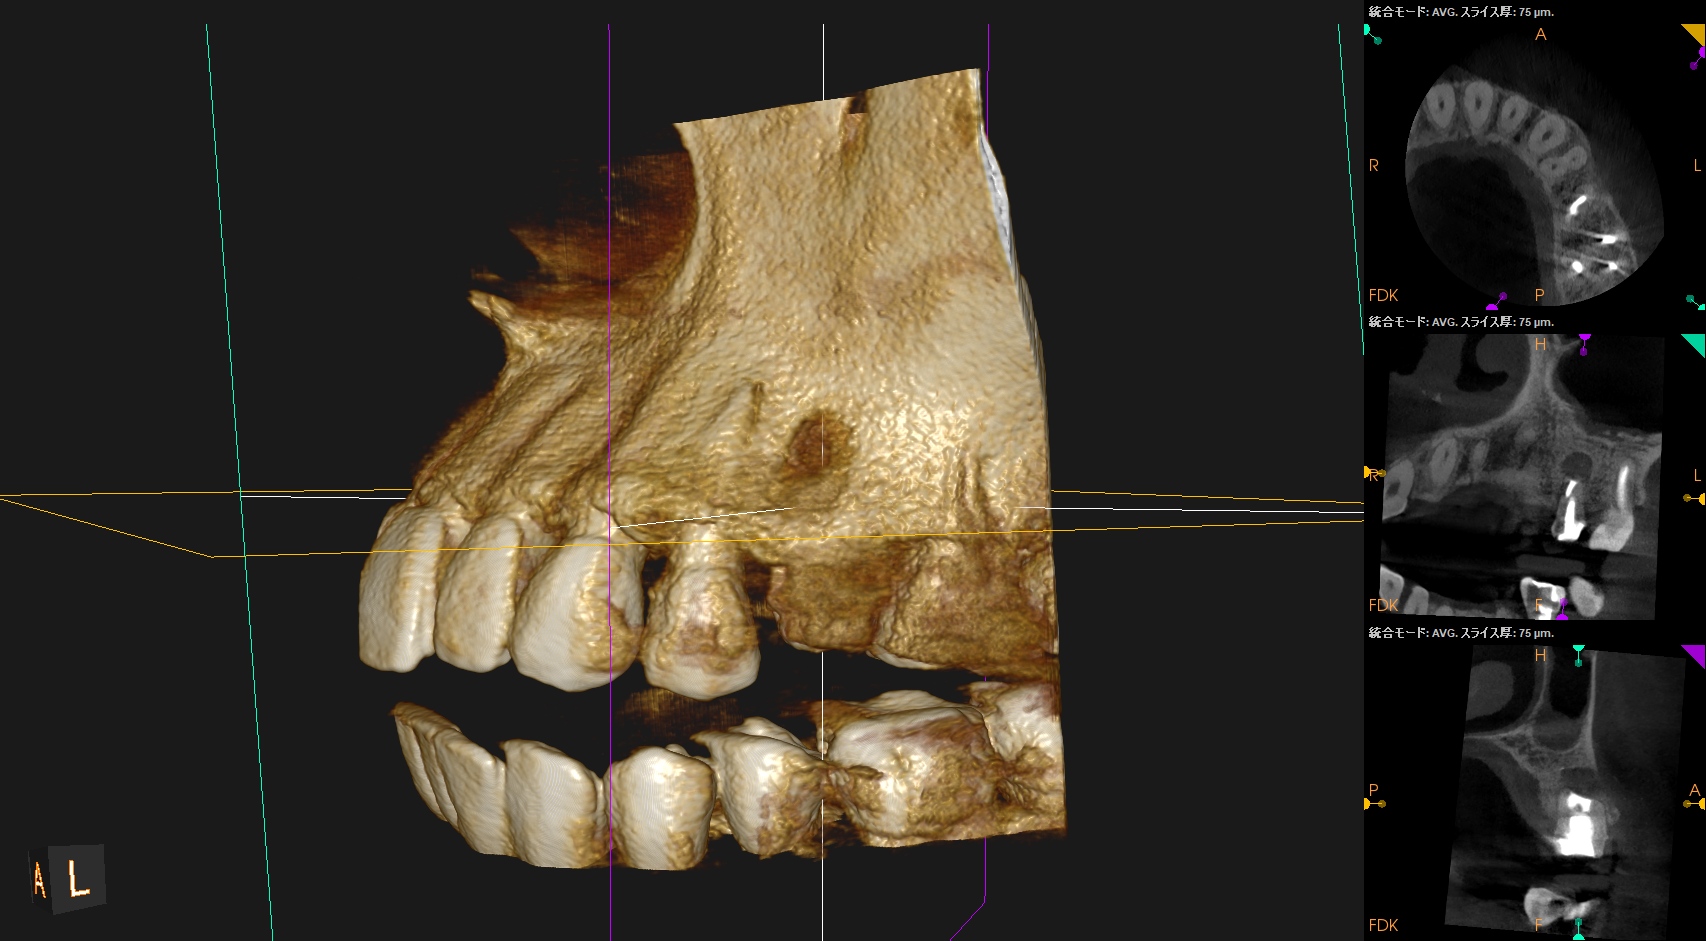

#13 Apicoectomy 5M recall(2025.12.8)

初診時と比較した。

劇的に歯槽骨が回復している。